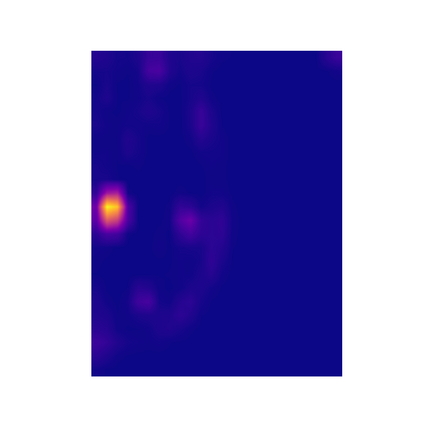

Breast cancer is the most widespread neoplasm among women and early detection of this disease is critical. Deep learning techniques have become of great interest to improve diagnostic performance. Nonetheless, discriminating between malignant and benign masses from whole mammograms remains challenging due to them being almost identical to an untrained eye and the region of interest (ROI) occupying a minuscule portion of the entire image. In this paper, we propose a framework, parameterized hypercomplex attention maps (PHAM), to overcome these problems. Specifically, we deploy an augmentation step based on computing attention maps. Then, the attention maps are used to condition the classification step by constructing a multi-dimensional input comprised of the original breast cancer image and the corresponding attention map. In this step, a parameterized hypercomplex neural network (PHNN) is employed to perform breast cancer classification. The framework offers two main advantages. First, attention maps provide critical information regarding the ROI and allow the neural model to concentrate on it. Second, the hypercomplex architecture has the ability to model local relations between input dimensions thanks to hypercomplex algebra rules, thus properly exploiting the information provided by the attention map. We demonstrate the efficacy of the proposed framework on both mammography images as well as histopathological ones, surpassing attention-based state-of-the-art networks and the real-valued counterpart of our method. The code of our work is available at https://github.com/elelo22/AttentionBCS.